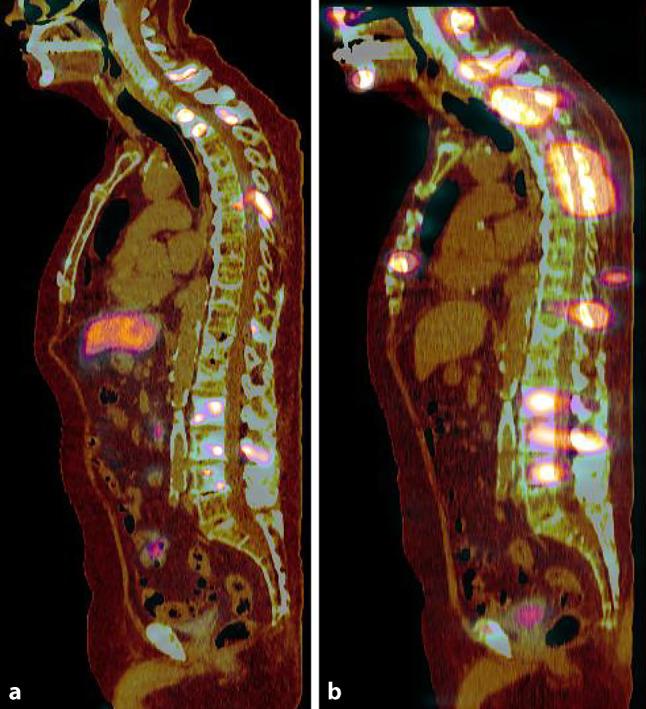

Prostate cancer (PCa) remains a leading cause of cancer-related morbidity and mortality in men. Over the past decades, the incidence has risen in all age groups. Prostate-specific membrane antigen (PSMA)-based theranostics, which involve the use of PSMA-targeting radiopharmaceuticals for both diagnostic imaging and therapeutic applications, have become integral in the management of patients with metastatic castration-resistant prostate cancer (mCRPC). The field has witnessed a substantial and continuously expanding body of scientific literature, encompassing case reports, original research, systematic reviews and also clinical guidelines. The objective of this joint statement is to enhance awareness of PSMA theranostics and underscore their critical role in contemporary precision oncology. We aim to provide a comprehensive yet practical perspective on the current landscape of PSMA-based diagnostic and therapeutic modalities, offering a consensus-driven approach to their clinical application.

前列腺癌(PCa)仍然是男性癌症相关发病和死亡的主要原因。在过去几十年中,各年龄组的发病率均有所上升。基于前列腺特异性膜抗原(PSMA)的诊疗方法,即使用靶向PSMA的放射性药物进行诊断成像和治疗应用,已成为转移性去势抵抗性前列腺癌(mCRPC)患者管理中不可或缺的一部分。该领域见证了大量且不断扩展的科学文献,包括病例报告、原创研究、系统评价以及临床指南。本联合声明的目的是提高对PSMA诊疗方法的认识,并强调其在当代精准肿瘤学中的关键作用。我们旨在就基于PSMA的诊断和治疗方式的当前形势提供一个全面而实用的观点,为其临床应用提供一种基于共识的方法。